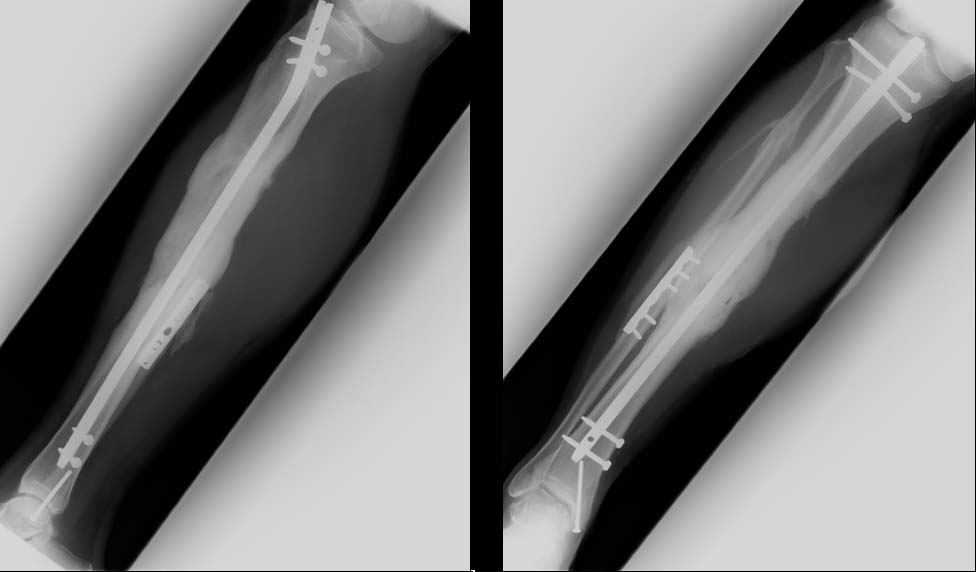

Here's one that we've shown this list before...this patient consolidated his defect with a single allo/auto combination direct defect grafting @ 6 weeks.

It's anecdotal, but can work-

Big defect, but if no active or history of pin tract infection, I think it is reasonable to remove fixator, align, IMN and huge graft as Chip demonstrated can work.